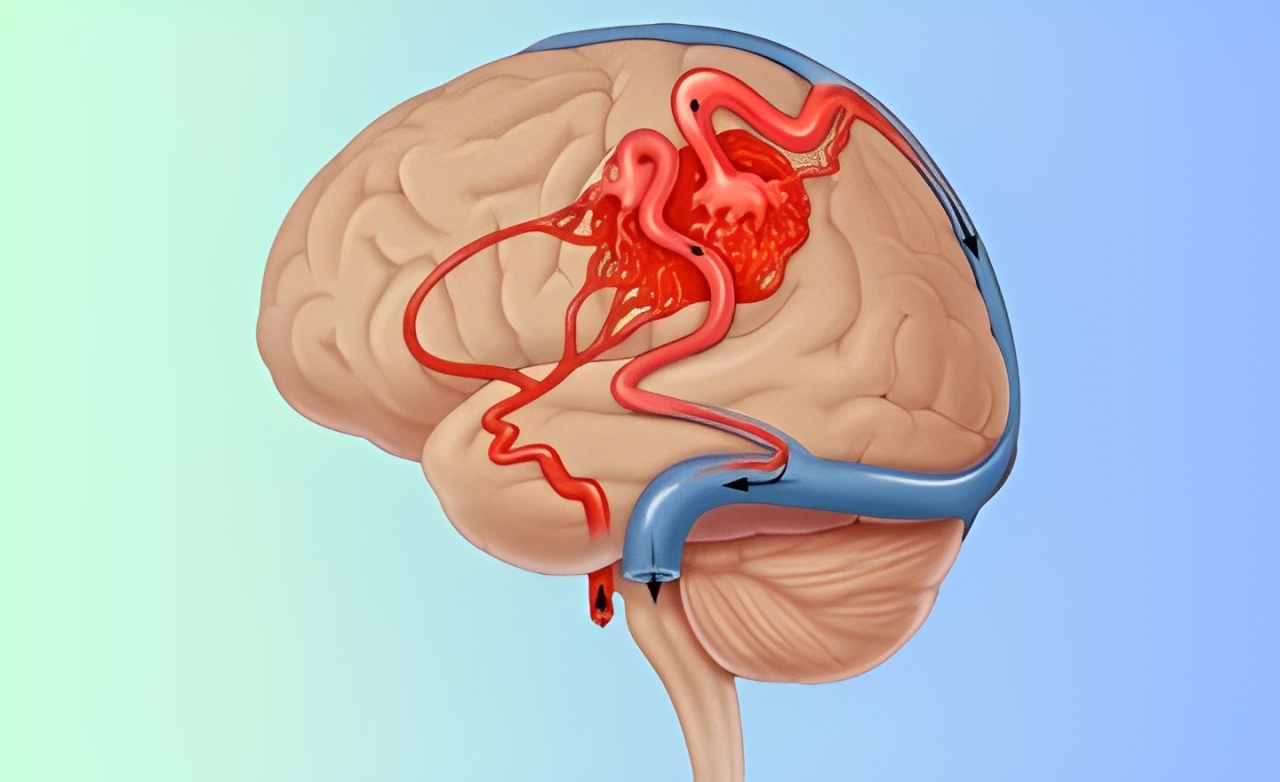

Abnormal tangling of arteries and veins in the brain, disrupting flow, causing headaches, seizures, or hemorrhage.

Blocks abnormal blood vessel connections to reduce bleeding risks, shrink the malformation, and prepare for further treatment if needed.